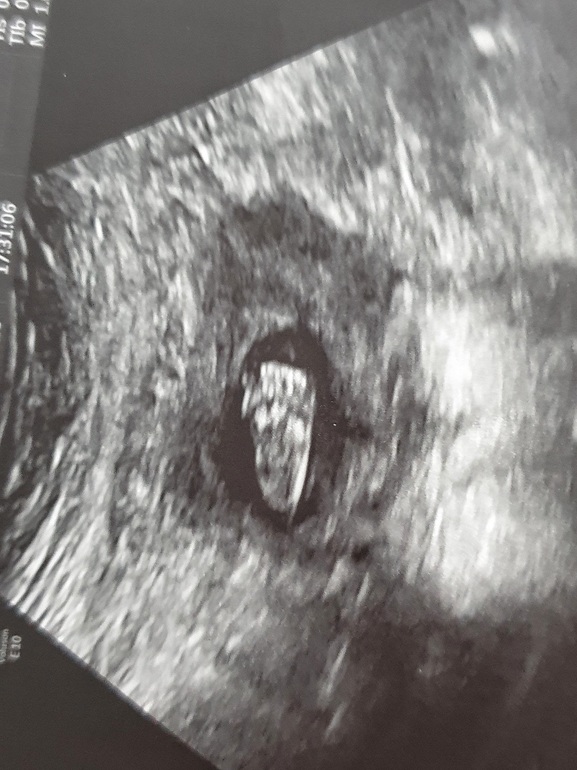

Ну а пока все нормально, жду шевелений, прислушиваюсь периодически, но пока непонятно, наверное кишечник)) сходили в 16 недель на свидание с крошкой, у нее все хорошо 🤞 (делала узи с доплерометрией), а мне написали две миомы 8 и 11 мм(( Как я поняла все равно пока их наблюдать только, и размер маленький, но я не в восторге от того, что их не было раньше и вот появились.